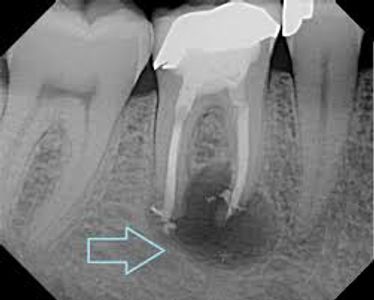

An abscess is a pocket of pus that forms around the root of an infected tooth. While pain and swelling are common signs, you may not have any symptoms. Sometimes an abscess causes a pimple-like bump on your gum that is visible. It is important to get the abscess treated and complete the recommended treatment to help prevent the infection from reoccurring.